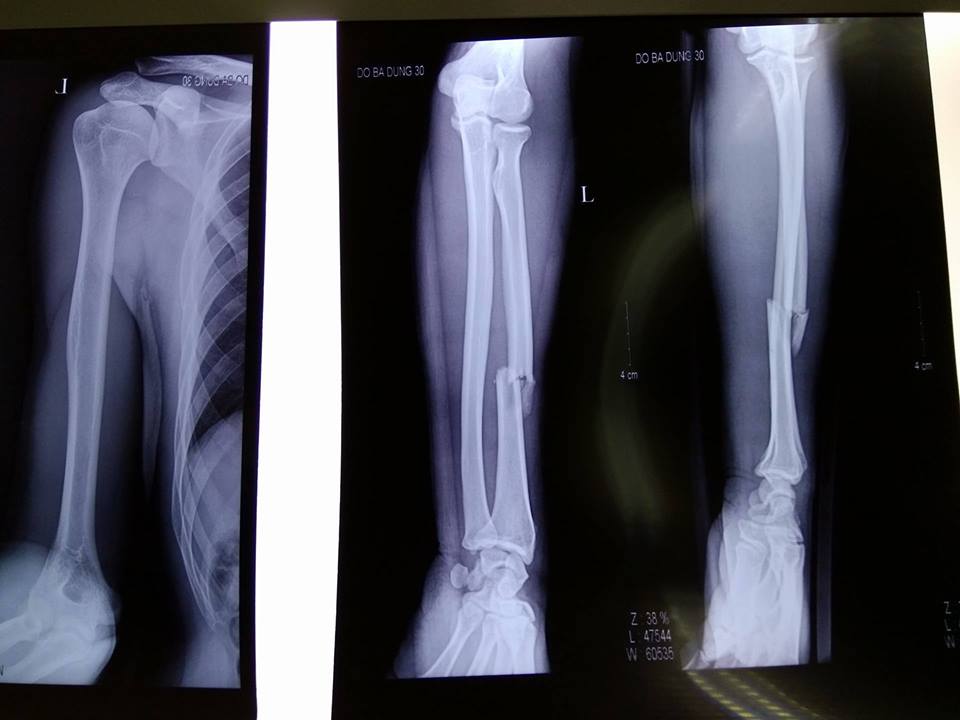

Click vào ảnh để xem 4 hình ảnh minh họa

Bác sĩ vật lý trị liệu hoặc bác sĩ chuyên khoa sẽ khám kỹ vết thương cùng cới chụp X-quang để chẩn đoán gãy xương trụ. Trong một số trường hợp, bạn có thể cần phải thực hiện thêm xét nghiệm như chụp MRI, CT hoặc xạ hình xương để hỗ trợ chẩn đoán và đánh giá mức độ nghiêm trọng của thương tích.

Trong quá trình điều trị, bác sĩ sẽ thường xuyên kiểm tra xương bằng X-quang để đảm bảo xương lành đúng vị trí.